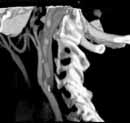

Восемь срезов в секунду и четвертьсекундные срезы фактически не содержащие артефактов движения.

Универсальная Адаптивная Матрица Детектора (AAD) использует восемь рядов датчика четырех различных размеров, для достижения лучших результатов при сканировании больших объемов.

Плавающее фокальное пятно позволяет получить изображения с высоким разрешением даже при субсекундном сканировании. Более того, Volume Zoom обеспечивает режим субмиллиметрового сканирования, и позволяет получить изображения с высоким разрешением (30 пар линий/см).